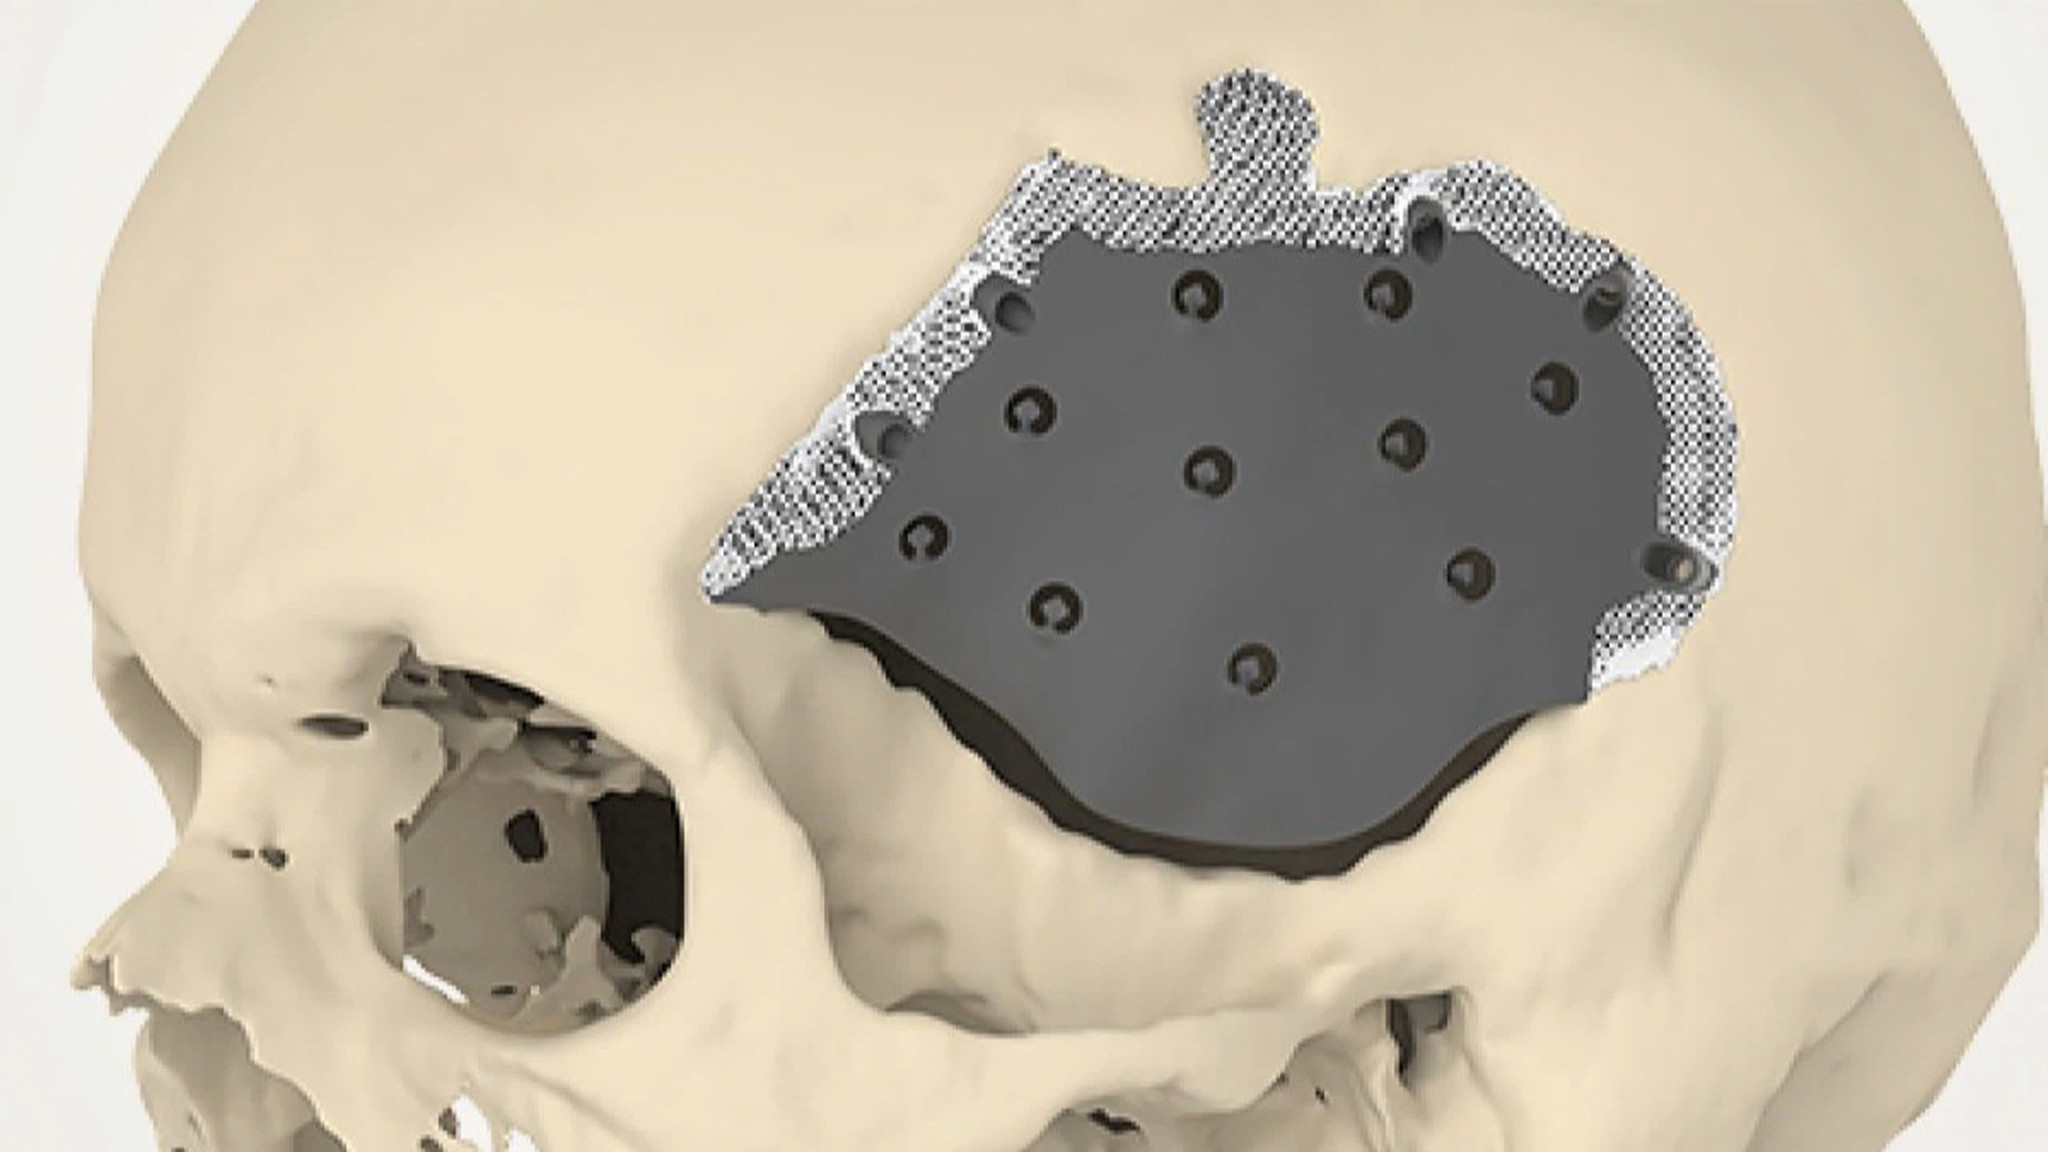

Nếu như bệnh tiêu xương sọ gây ra tình trạng khuyết xương sọ thì bạn có thể sẽ cần đến phẫu thuật tạo hình phần sọ đã bị khuyết như ghép sọ tự thân, ghép sọ bằng mảnh ghép nhân tạo.

Phẫu thuật ghép sọ là một phương pháp điều trị bệnh